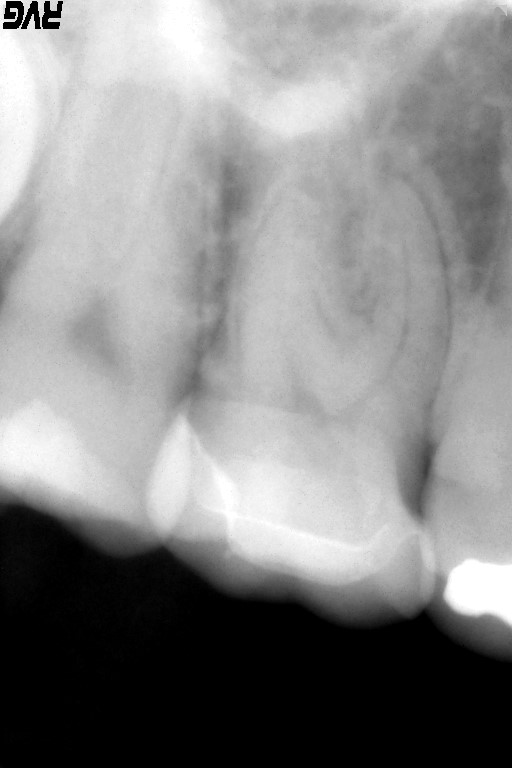

術前のレントゲン:近心頬側根に炎症があるように観えます。

麻酔をした後にラバーダム防湿を行い、随腔内(神経がある空間)を探索すると健全な歯髄(歯の神経)は診られず、腐敗した組織が確認できます。